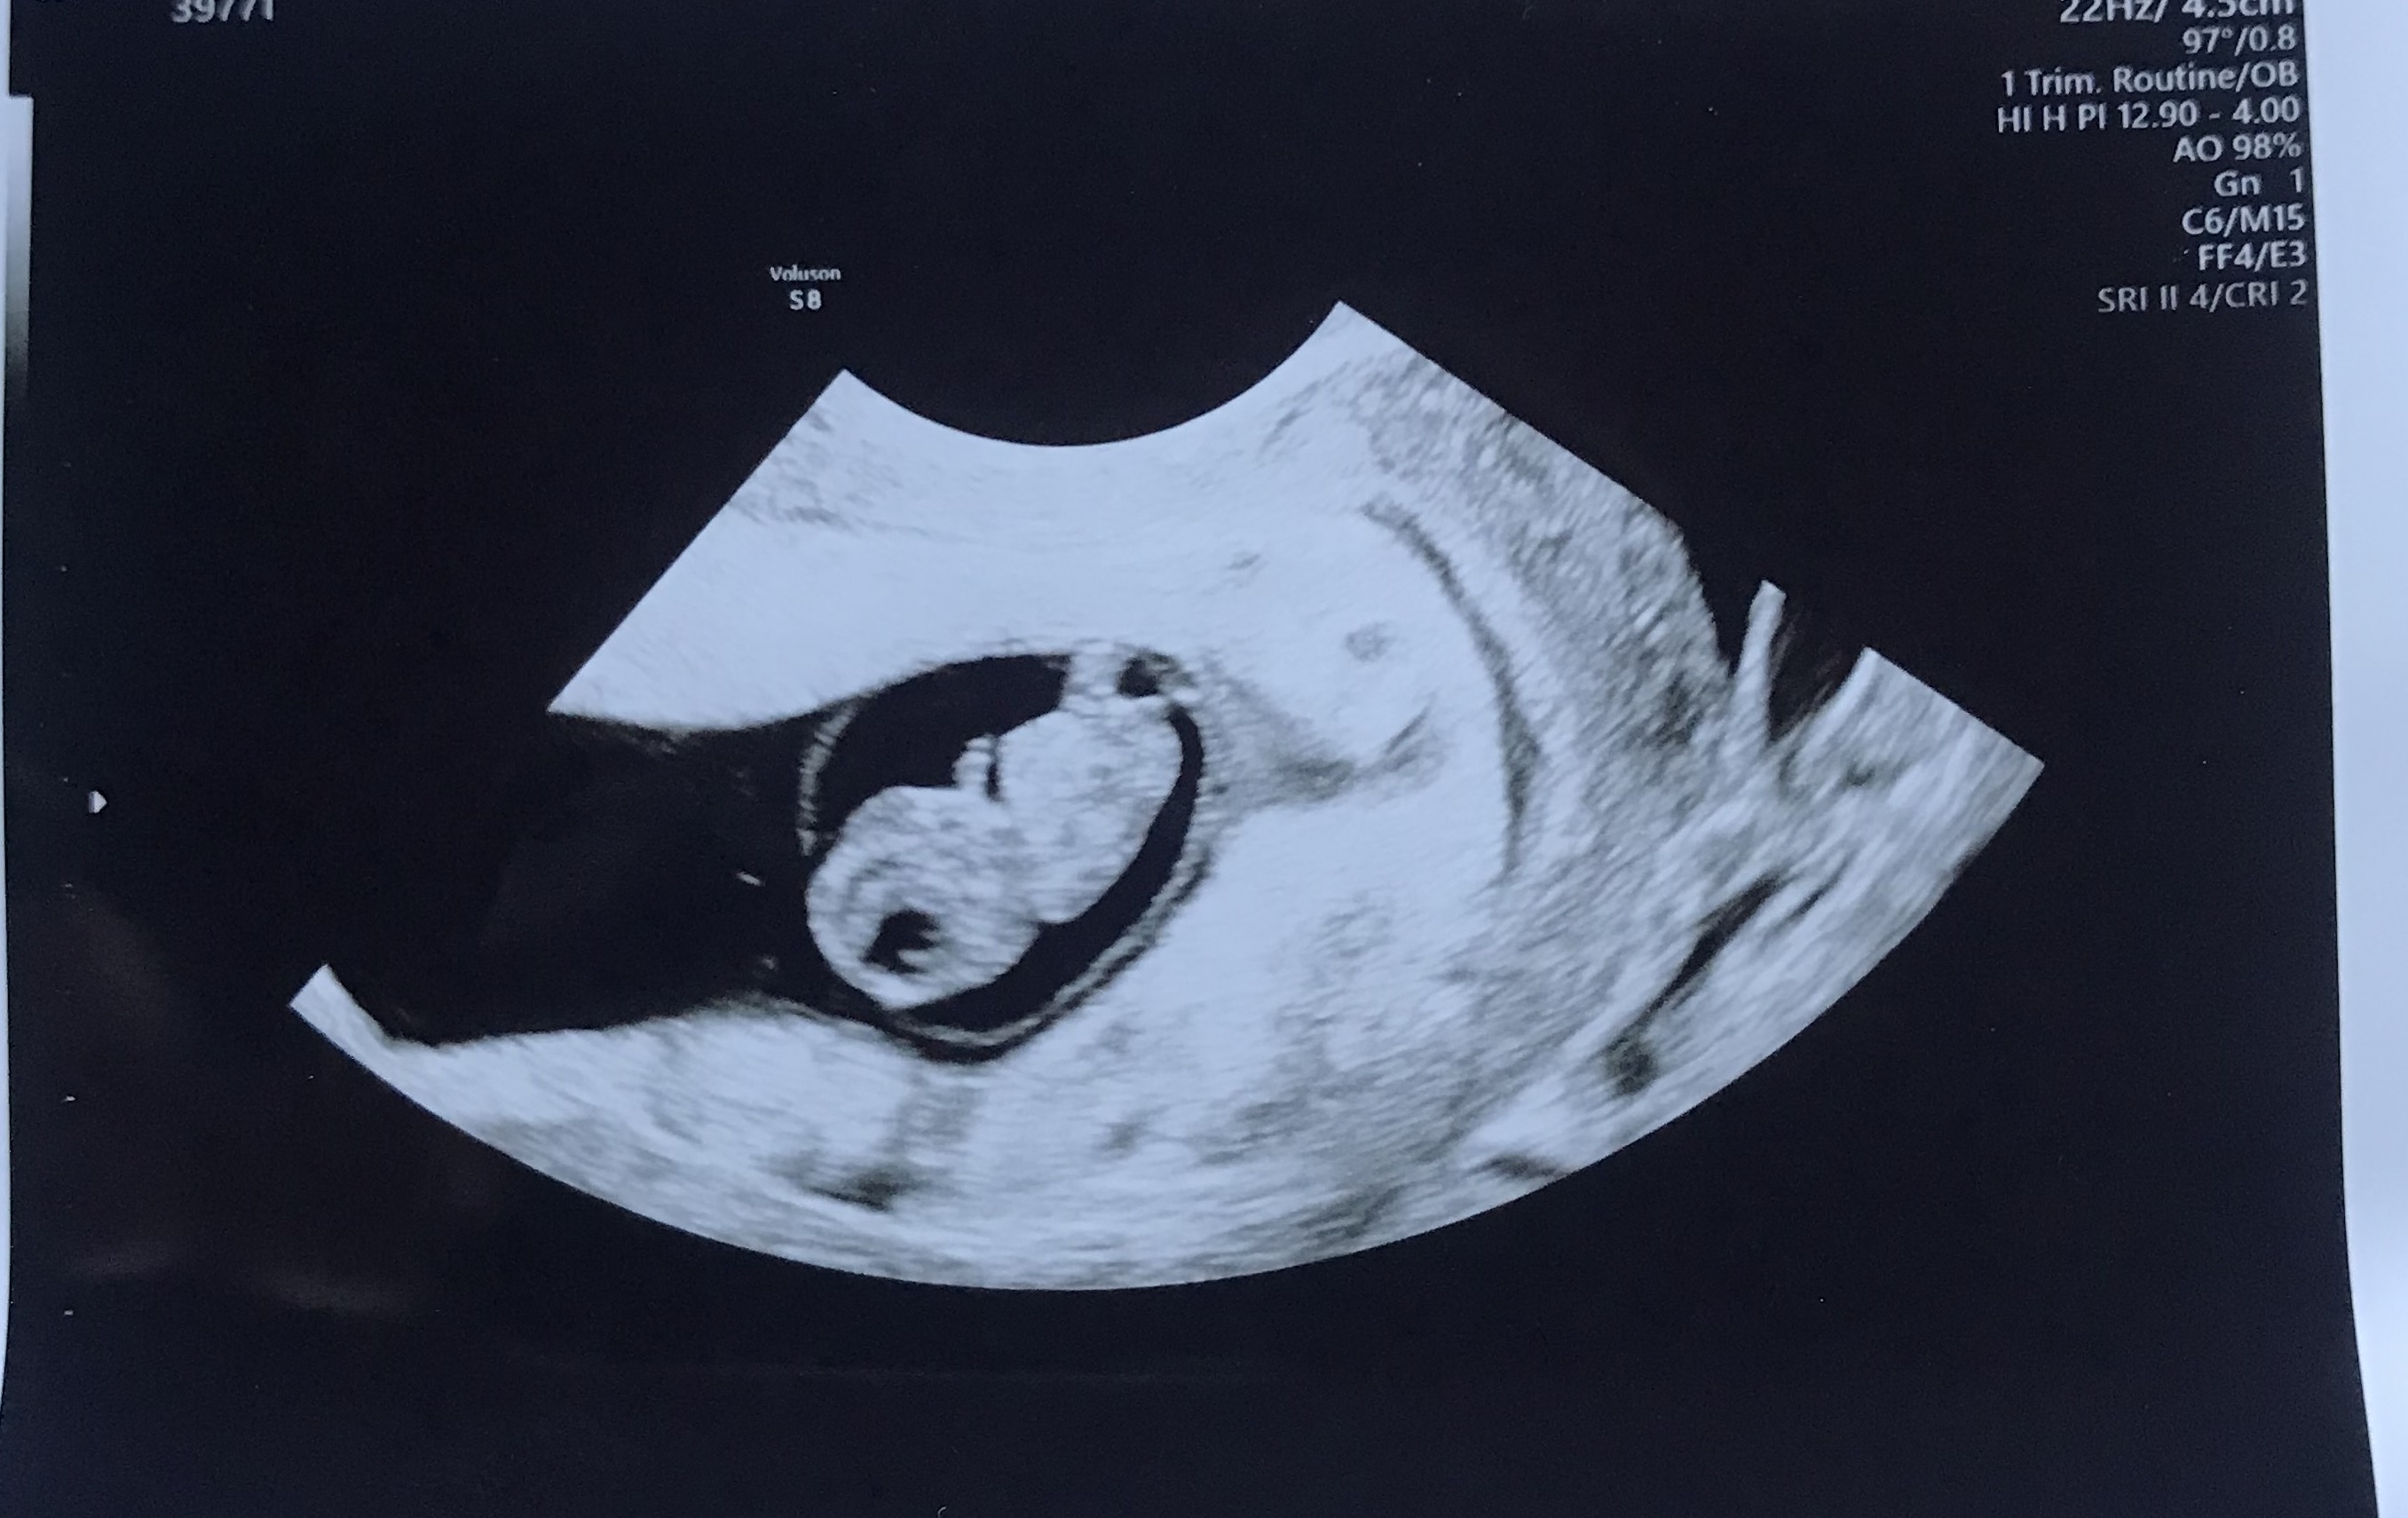

Weekly ultrasounds! Doing IVF, I was able to watch my baby grow each week. Every Monday morning, we'd pile ourselves into the car and drive to the clinic. I'd sit on the table in the dark room, heart racing. Deep breathes. Just waiting to see her. Just praying that little heartbeat would still be flickering on the screen.

She changed from a tiny blob to a gummy bear to an alien to a small person. Her little arms and hands wiggling around on the screen. Her heartbeat racing away - living her little life as best she could in her little home.

Seeing her move on the screen was the coolest T1 moment. That little blob was just sitting there, then suddenly the limbs wiggled and twisted. It was a real person, finally. Not just a cluster of cells sitting in a freezer somewhere.